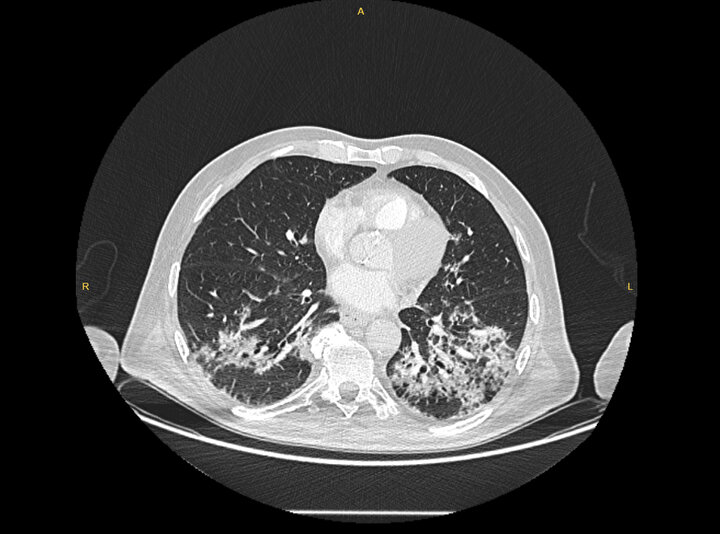

Kliniğe yeni başvuran bir hastanın, 5 Ağustos'ta çekilen tomografi görüntülerindeki tipik koronavirüs görüntülerinin olduğunu ifade eden Karalezli, hastanın bir hafta içerisindeki tomografi görüntüsünde ciddi değişiklik olduğunu ve enfeksiyonun çok arttığını söyledi.

Tedavisine rağmen nefes darlığı şikayetleri devam eden bir hastaya uygulanan akciğer görüntülemesinde hastanın her iki akciğerinin büyük bir bölümünü enfeksiyon kapladığını tespit ettiklerini ifade eden Karalezli, "Bu hastalığın sonunun ne olduğunu bilmiyoruz. Akciğer tutulumları, bu şekilde olduğu zaman hastaları oksijen tedavisi ile gönderiyoruz. Çok yeni bir hastalık olduğu için bu seyir nasıl olacak? Geriye dönüş var mı? Takiplerle öğrenebileceğimiz bir durum." dedi.